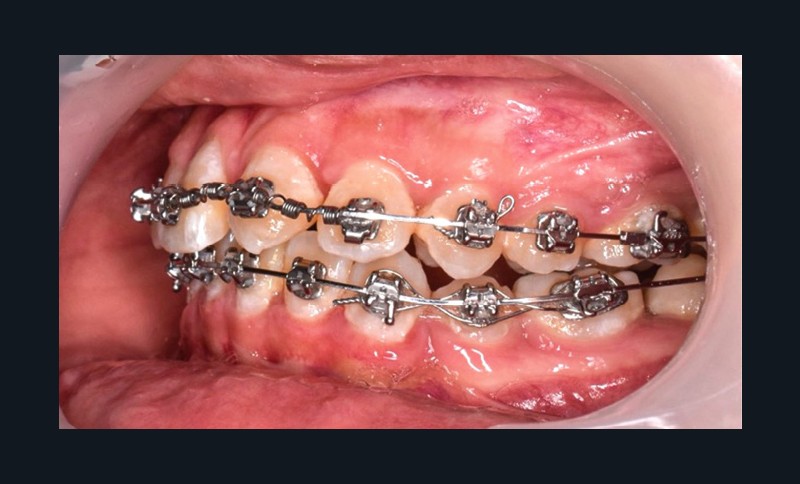

L’objectif du traitement est la correction de la DDA tout en assurant le remplacement de la 21 compromise. Décision a été prise d’extraire 34 et 44, ainsi que 21 et 14. La traction de la 23 a été réalisée à l’aide de forces légères, sur un arc transpalatin (fig. 9). Le nivellement et l’alignement, puis une mécanique par glissement ont permis d’aménager l’espace suffisant à la stratification de la canine. Elle associait un ressort en nickel-titane à des élastiques de Classe II (4 ½ oz, 3/16’’) sur un arc en acier .019×.025. Une phase d’ingression a été réalisée pour ajuster le niveau du bord libre de la canine à celui de l’incisive controlatérale (fig. 10-12).